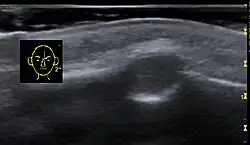

Periorbitale Dermoidzyste

Eine Dermoidzyste kann sich auch im Kopfbereich (Nichtodontogene Zysten) ausbilden.

Zusammen mit den Epidermoidzysten stellen Dermoidzysten etwa 20 Prozent der Raumforderungen am knöchernen Schädel. In der Regel treten sie bereits bei Säuglingen und Kleinkindern in Erscheinung als umschriebene, anfangs verschieblich, dann nicht mehr verschiebliche glatt begrenzte Knotenbildung typischerweise in Augenbrauenhöhe im Bereich der gesamten Schädelkonvexität.[6]

Differentialdiagnostisch ist bei Lokalisation in Nähe der Nasenwurzel an eine Enzephalozele zu denken.